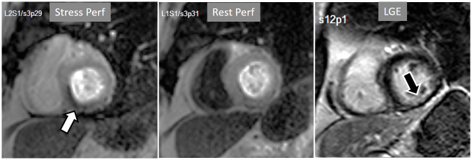

The presence of inducible residual peri-infarction ischemia in a territory with a previous MI has been addressed by the consideration of the extension of a stress perfusion defect in comparison with that of the LGE. Those defects with equal size on both sequences would be labelled as “fixed” (Fig. 16), while those perfusion defects exceeding the area of MI would be considered as “partially reversible” (Fig. 17), independently of rest perfusion studies. The diagnostic performance of the latter finding for the diagnosis of a residual significant stenosis in the infarct-related artery has been found to be adequate, though a good deal of cases with apparently fixed defects had also significantly obstructed arteries [46].

Fig. 16.Stress/Rest perfusion in chronic myocardial infarction. Perfusion defect during stress (performed in first place) (black arrow), not present at rest, matching the area of LGE (white arrow) in a case of large anterior subendocardial MI.

Fig. 17.Stress/Rest perfusion in chronic myocardial infarction. Perfusion defect during stress (performed in first place) (white arrow), not present at rest, fairly larger than the region of LGE (black arrow) in a patient with a subendocardial inferior MI.